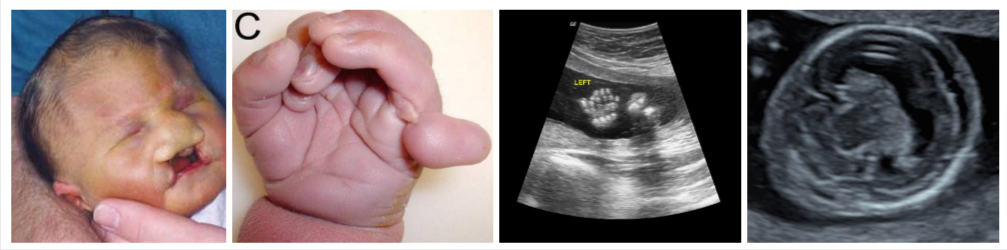

รูปแรก : ศีรษะทารกมีขนาดเล็ก

รูปที่ 2 : นิ้วมือซ้อนกัน และมีนิ้วเกิน

รูปที่ 3 : แสดงรูปอัลตราซาวนด์มีนิ้วเกิน

รูปที่ 4 : แสดงรูปอัลตราซาวนด์ที่มีสมองผิดปกติ สมองไม่แบ่งเป็น 2 ซีก

ทารกที่เป็นโรค Patau syndrome จะมีปัญหาเกี่ยวกับสุขภาพได้ในหลายอวัยวะ เริ่มตั้งแต่การเจริญเติบโตในครรภ์มักจะช้าผิดปกติ ทำให้น้ำหนักแรกเกิดต่ำ และ 80% จะมีความบกพร่องของหัวใจอย่างรุนแรง, สมองมักไม่แบ่งเป็น 2 ซีกซึ่งเรียกว่า holoprosencephaly, และส่งผลต่อลักษณะใบหน้าและทำให้เกิดข้อบกพร่อง เช่น

- ปากแหว่งเพดานโหว่

- ตาเล็กผิดปกติ (microphthalmia)

- ไม่มีตา 1 ข้างหรือทั้งสองข้าง (anophthalmia)

- ระยะห่างระหว่างดวงตาน้อยกว่าปกติ (hypotelorism)

- นอกจากนี้ยังอาจมีความผิดปกติของมือและเท้าเช่นนิ้วหรือนิ้วเท้าพิเศษ (polydactyly) และก้นโค้งมนไปจนถึงเท้าที่เรียกว่า Rocker-bottom feet